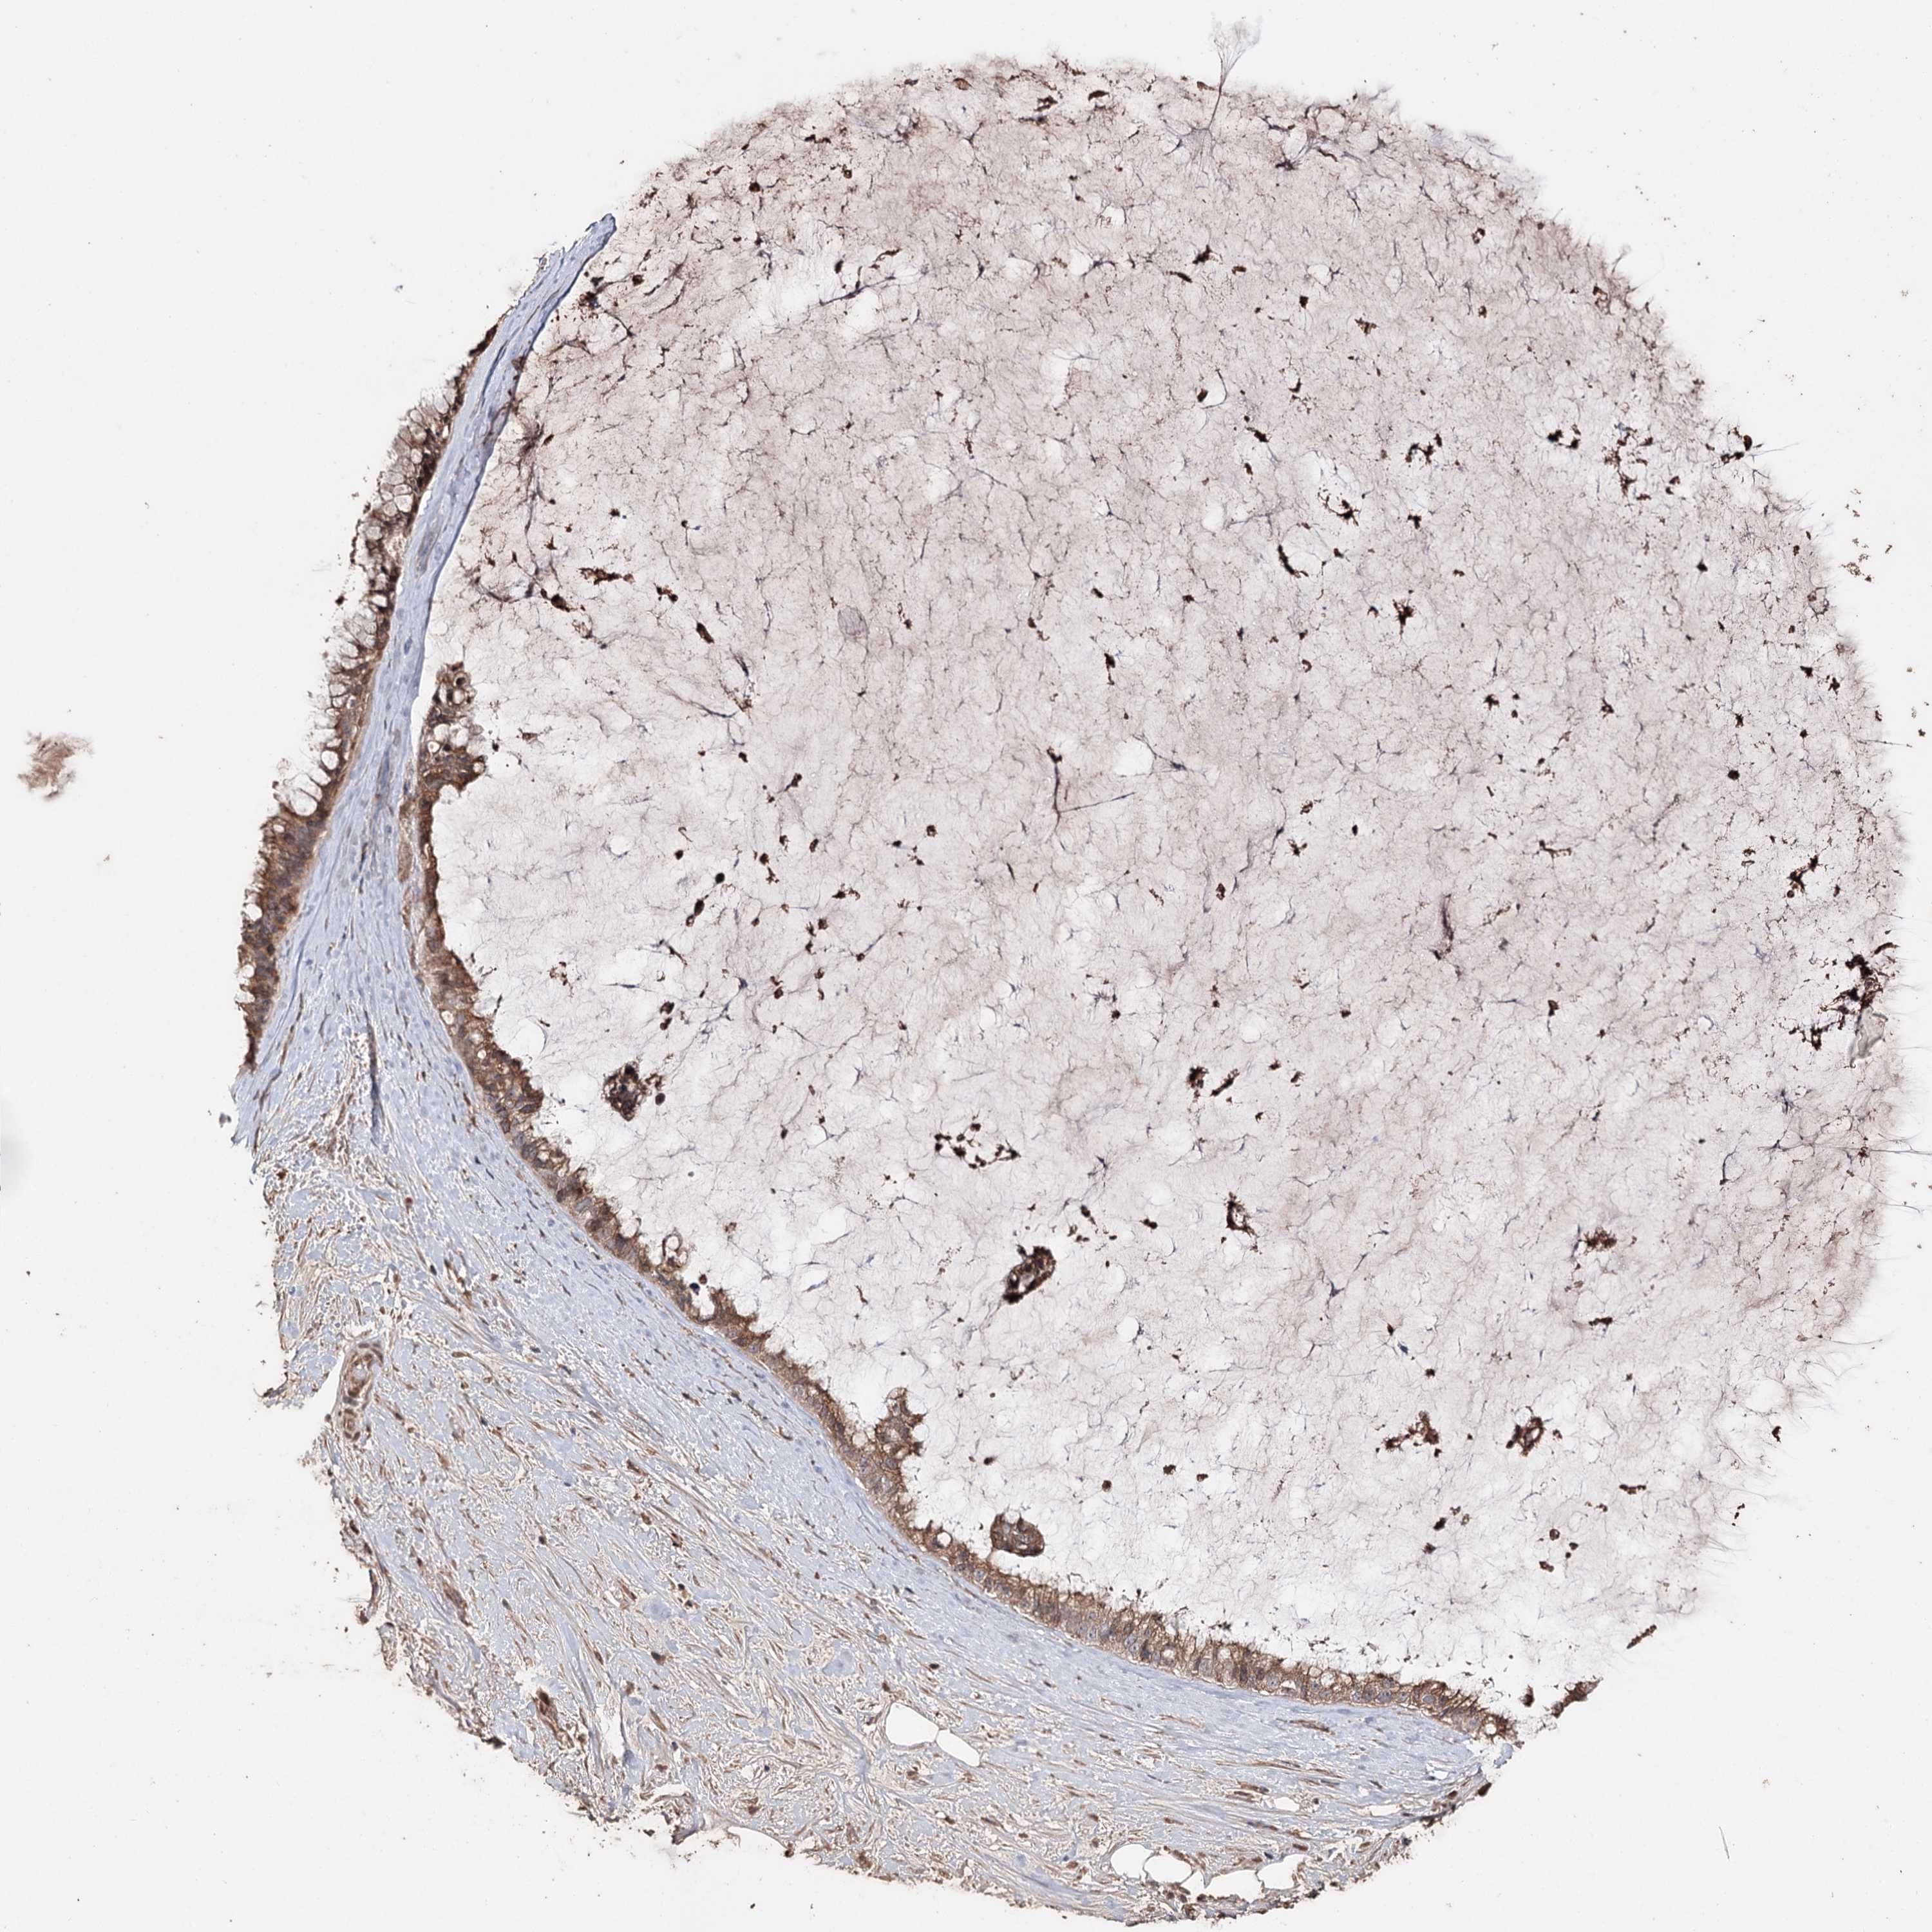

OVARIAN CANCER - Protein expressioni

A mouse-over function shows sample information and annotation data. Click on an image to view it in a full screen mode. Samples can be filtered based on level of antibody staining by selecting one or several of the following categories: high, medium, low and not detected. The assay and annotation is described here.

Note that samples used for immunohistochemistry by the Human Protein Atlas do not correspond to samples in the TCGA dataset.

Antibody stainingi

Antibody staining in the annotated cell types in the current human tissue is reported as not detected, low, medium, or high, based on conventional immunohistochemistry profiling in selected tissues. This score is based on the combination of the staining intensity and fraction of stained cells.

Each image is clickable and will lead to virtual microscopy that enables deeper exploration of all samples and also displays staining intensity scores, fraction scores and subcellular localization as well as patient and tissue information for each sample.

Antibody HPA005480

Cystadenocarcinoma, serous, NOS

Carcinoma, endometroid

Carcinoma, NOS

Cystadenocarcinoma, mucinous, NOS